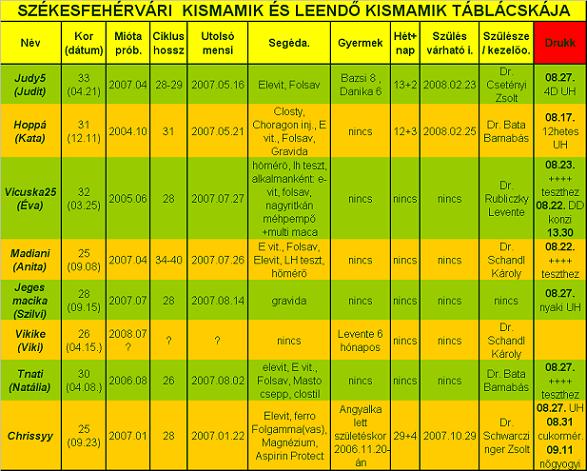

Ha valaki nem tudná "kiolvasni", mit lát, segítek: az első képen a drágánk feje jobb ldalt (a másikon is

) , aztán a kis teste, a cicije felett a pici folt az egyik keze, aztán egy nagy pocak, majd valahogy a lábai (egy pár lábujjacskája látható!

)

A másik képenközelebbről van a buksija, lehet látni a nóziját, meg az éppen csókra álló száját!!

Ja, és amikor uh-zott a doki, kitátotta a száját, vissza is játszotta BB, mondta, hogy tök érdekes, még ilyen pici, és nyitogatja a száját! Hát egész nap vigyorogtunk, úgy örültünk! Tényleg nagyon jó volt látni!

Ő a kisfiúnk, csak így tudtuk lefotózni, ennél jobban nem mutatta a kis pofiját.

Ő a kisfiúnk, csak így tudtuk lefotózni, ennél jobban nem mutatta a kis pofiját.